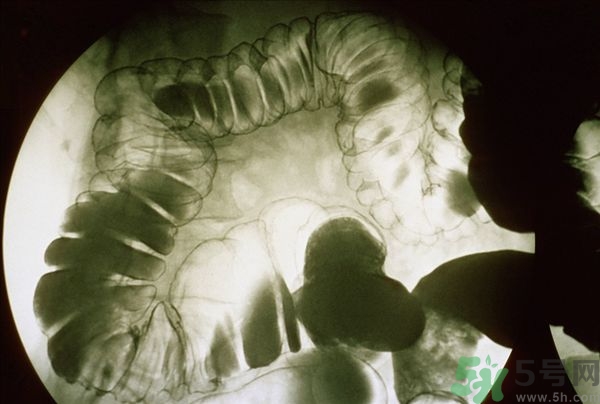

腸炎的分類其實有很多,比如盲腸炎、潰瘍性大腸炎、慢性腸炎、急性腸炎等等,是比較常發(fā)生的胃腸疾病,當我們的腹部出現劇痛的時候首先我們要確定是哪一種疾病,并且要及時的進行治療,腸炎嚴重的時候甚至有休克的可能,下面我們就來說說當腸炎患者出一了腹前的時候應該怎么緩解與治療。